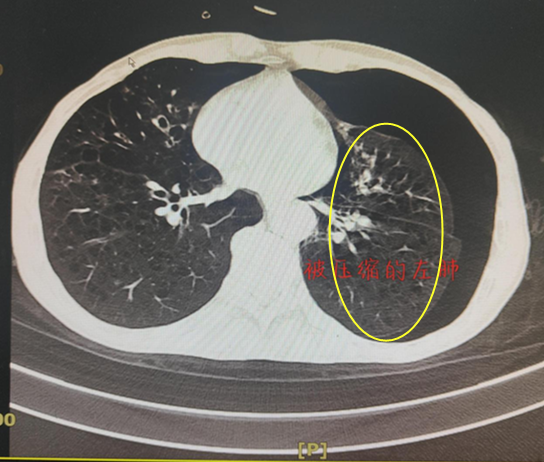

“今天吸氧,感觉没那么喘了”。邓大爷虽不了解吸氧与吸氧之间有何区别,但自觉气促症状好转。事实证明,他的感觉是对的,联合经鼻高流量湿化氧疗后,邓大爷胸腔闭式引流瓶中逐渐无水柱波动及气泡冒出,气胸症状明显改善。继续治疗4天后,复查胸部CT提示气胸已完全吸收,邓大爷顺利出院了。

CT复查提示左肺已完全复张